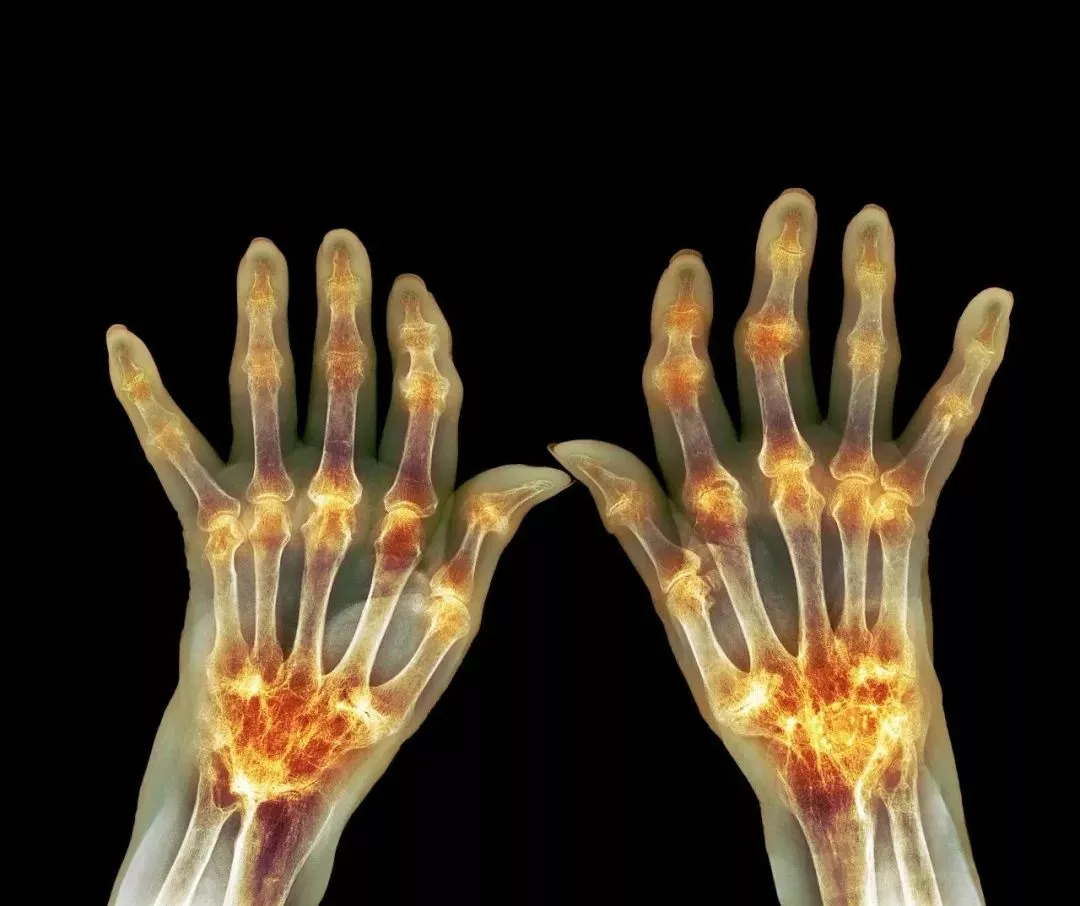

痛风的本质是体内尿酸水平升高 , 析出尿酸盐沉淀在关节、骨骼处 , 造成关节肿胀、疼痛的感觉 , 就如同老虎在撕咬关节一样 。

当人体尿酸代谢异常 , 尿酸盐首先就会沉积在关节中 , 形成尿酸结晶 , 从而引起关节肿大 。 最明显的就是脚关节肿大 , 还可能会伴有头痛、脑热、厌食等症状 。